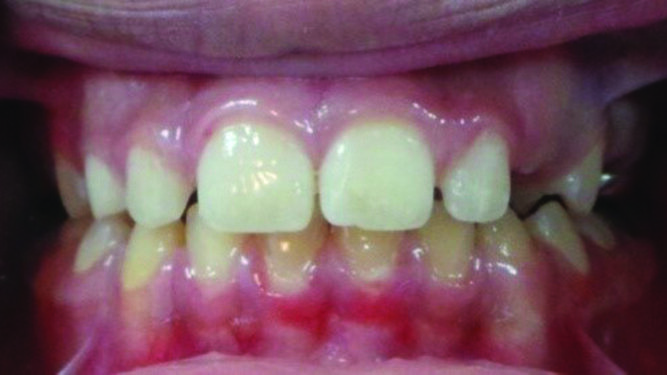

MIH was diagnosed based on clinical appearance. See Figures 1 (a, b, c, d & e) for clinical features. Figures 2 (a, b & c) for radiographic findings.A diagnostic list and treatment plan was formulated by a specialist of Paediatric dentist as well as orthodontist and explained in detailed to the father.

Fig. 1 (a, b, c, d & e). Showing a dislodged filling of 36. 16 yellowish brown hypomineralised lesions. 36 and46 large composite fillings.